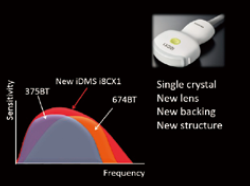

При поточному ультразвуковому дослідженні може виникнути потреба у зміні датчика в залежності від області обстеження або діагностичних цілей. У нашому дослідницькому центрі для виявлення новоутворень використовується датчик 3 МГц (PVT-375BT), а для більш детальної оцінки - датчик 6 МГц (PVT-674BT). Інноваційні розробки в архітектурі системи з новітньою технологією датчиків Intelligent Dynamic Micro-Slice (iDMS) сприяли створенню наступного покоління датчиків. Нещодавно представлений надширокосмуговий конвексний датчик PVI-475BX, доступний тільки в Aplio i-серії, охоплює обидва спектри, що покриваються двома звичайними конвексними датчиками (PVT-375BT і PVT-674BT), із вищою чутливістю.

Цей датчик містить монокристал і вдосконалені компоненти, які включають нову лінзу, п'єзоелектричний генератор, нові узгоджувальні шари і матеріал підкладки. Датчик "2-в-1" також використовує інноваційну архітектуру системи iBeam forming для забезпечення вузьких, однорідних ультразвукових променів високої щільності, де технологія iDMS посилює промінь у напрямку лінзи, забезпечуючи безперервне автоматизоване фокусування на будь-якій глибині одночасно. В результаті можна отримати високоякісні та однорідні зображення з високою чутливістю, контрастністю і просторовою роздільною здатністю в осьовому, поздовжньому і вертикальному вимірах (рис. 2).

Рисунок 1. Надширокосмуговий конвексний датчик PVI-475BX